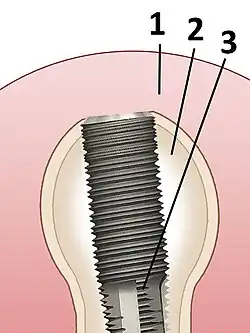

Zahnimplantat

1. Zahnfleisch;

2. Knochengewebe;

3. Schraubenförmiges Implantat aus Titan

Ein Zahnimplantat (lateinisch implantare ‚einpflanzen‘) ist ein in den Kieferknochen eingesetztes „alloplastisches Konfektionsteil“ (Implantat). Das Teilgebiet der Zahnheilkunde, das sich mit der Insertion (Einsetzen) von Zahnimplantaten in den Kieferknochen befasst, wird als Implantologie (von altgriechisch λόγος lógos, deutsch ‚Wort‘, ‚Lehre‘) bezeichnet. Durch ihre Verwendbarkeit als Träger von Zahnersatz übernehmen Zahnimplantate die Funktion künstlicher Zahnwurzeln. Hierzu werden sie entweder mittels Schraubgewinde in den Kieferknochen (enossale[1] Implantate) eingedreht oder eingesteckt. Sie verbinden sich innerhalb von 3 bis 6 Monaten mit dem umgebenden Knochen zu einer festen, äußerst belastbaren Trägereinheit (Osseointegration).

Von der Implantatform hängt die chirurgische Insertionstechnik ab. Aus der Gestalt des Abutments, des aus dem Kieferknochen herausragenden Implantatteils, resultiert die Anfertigung der Suprakonstruktion, des auf den Implantaten einzugliedernden Zahnersatzes. Zahnimplantate bestehen seit den 1980er Jahren üblicherweise aus Titan, aber auch aus keramischen Materialien oder Kunststoff (PEEK).[2]